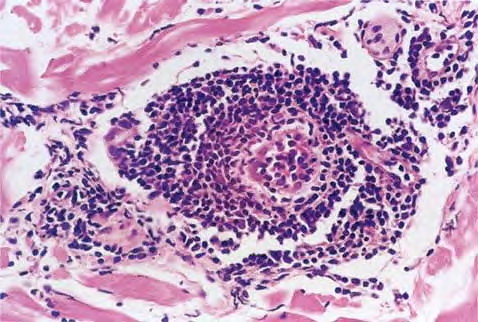

Erythema Chronicum Migrans =الحمامى المزمنة الهاجرة